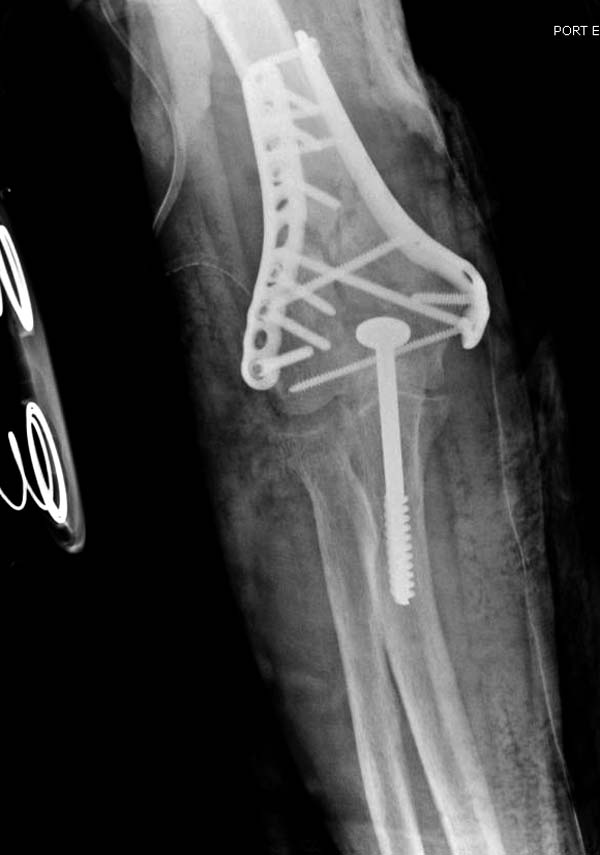

Примеры: первому более 15 лет фиксирован шурупом и tension band

technique, а второй перелом открытый больной 80 лет, после наружного

фиксатора в первом этапе и окончательная фиксация вторично. Третьий раз

внесуставная остеотомия...